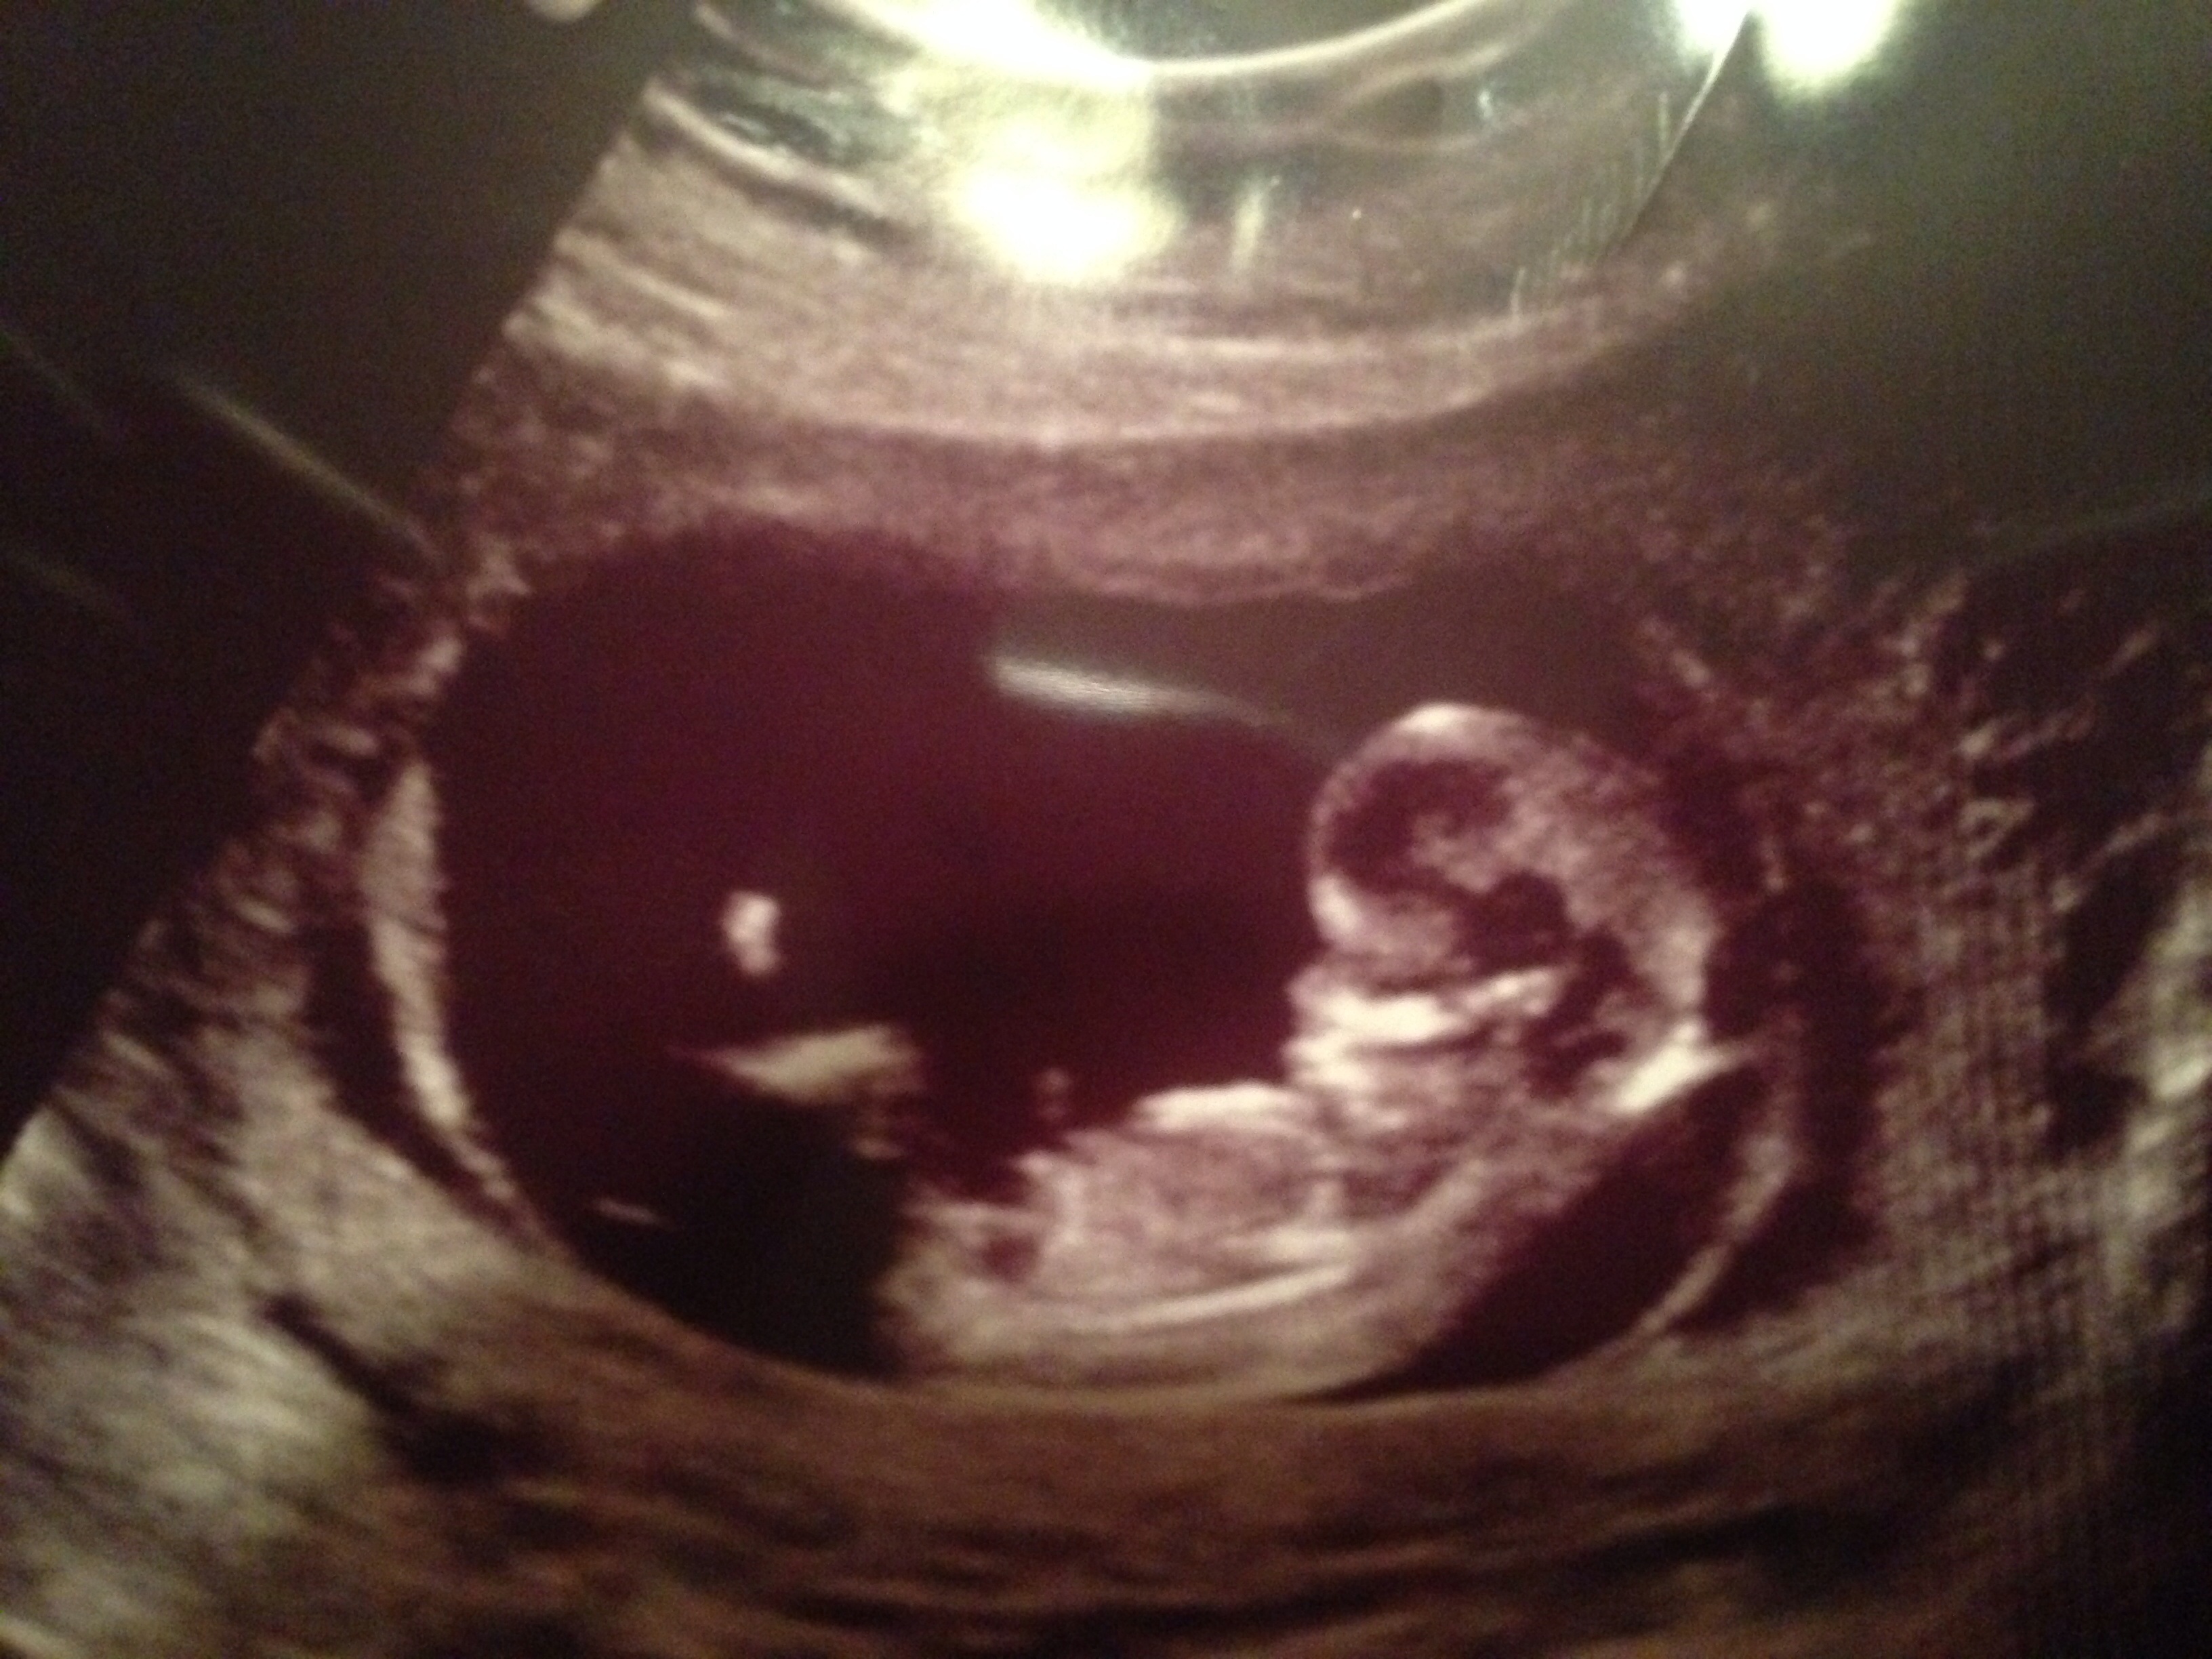

this is a 12week ultrasound I'm begging to know what I'm having Boy or Girl what are your guess I hear Turtle is who I need to look at my ultrasound ! 😊 Attachment 19972

I think boy!